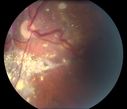

Ocular Lymphoma - non-Hodgkins - B-Cell447 viewsMultifocal sub-RPE lesions in the left eye of a patient with history of Non-hodgkins B-cell Lymphoma last active 2 years agoMar 09, 2017